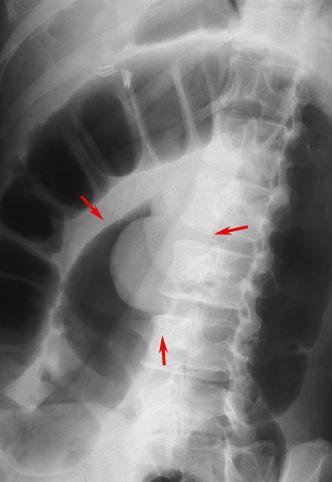

Tejido grasoso del Colon, que acompaña úlceras en la intusucepción y sus alrededores

Tumor no Epitelial Benigno/Lipoma

colon/descendente

Rayos X

35 - 40